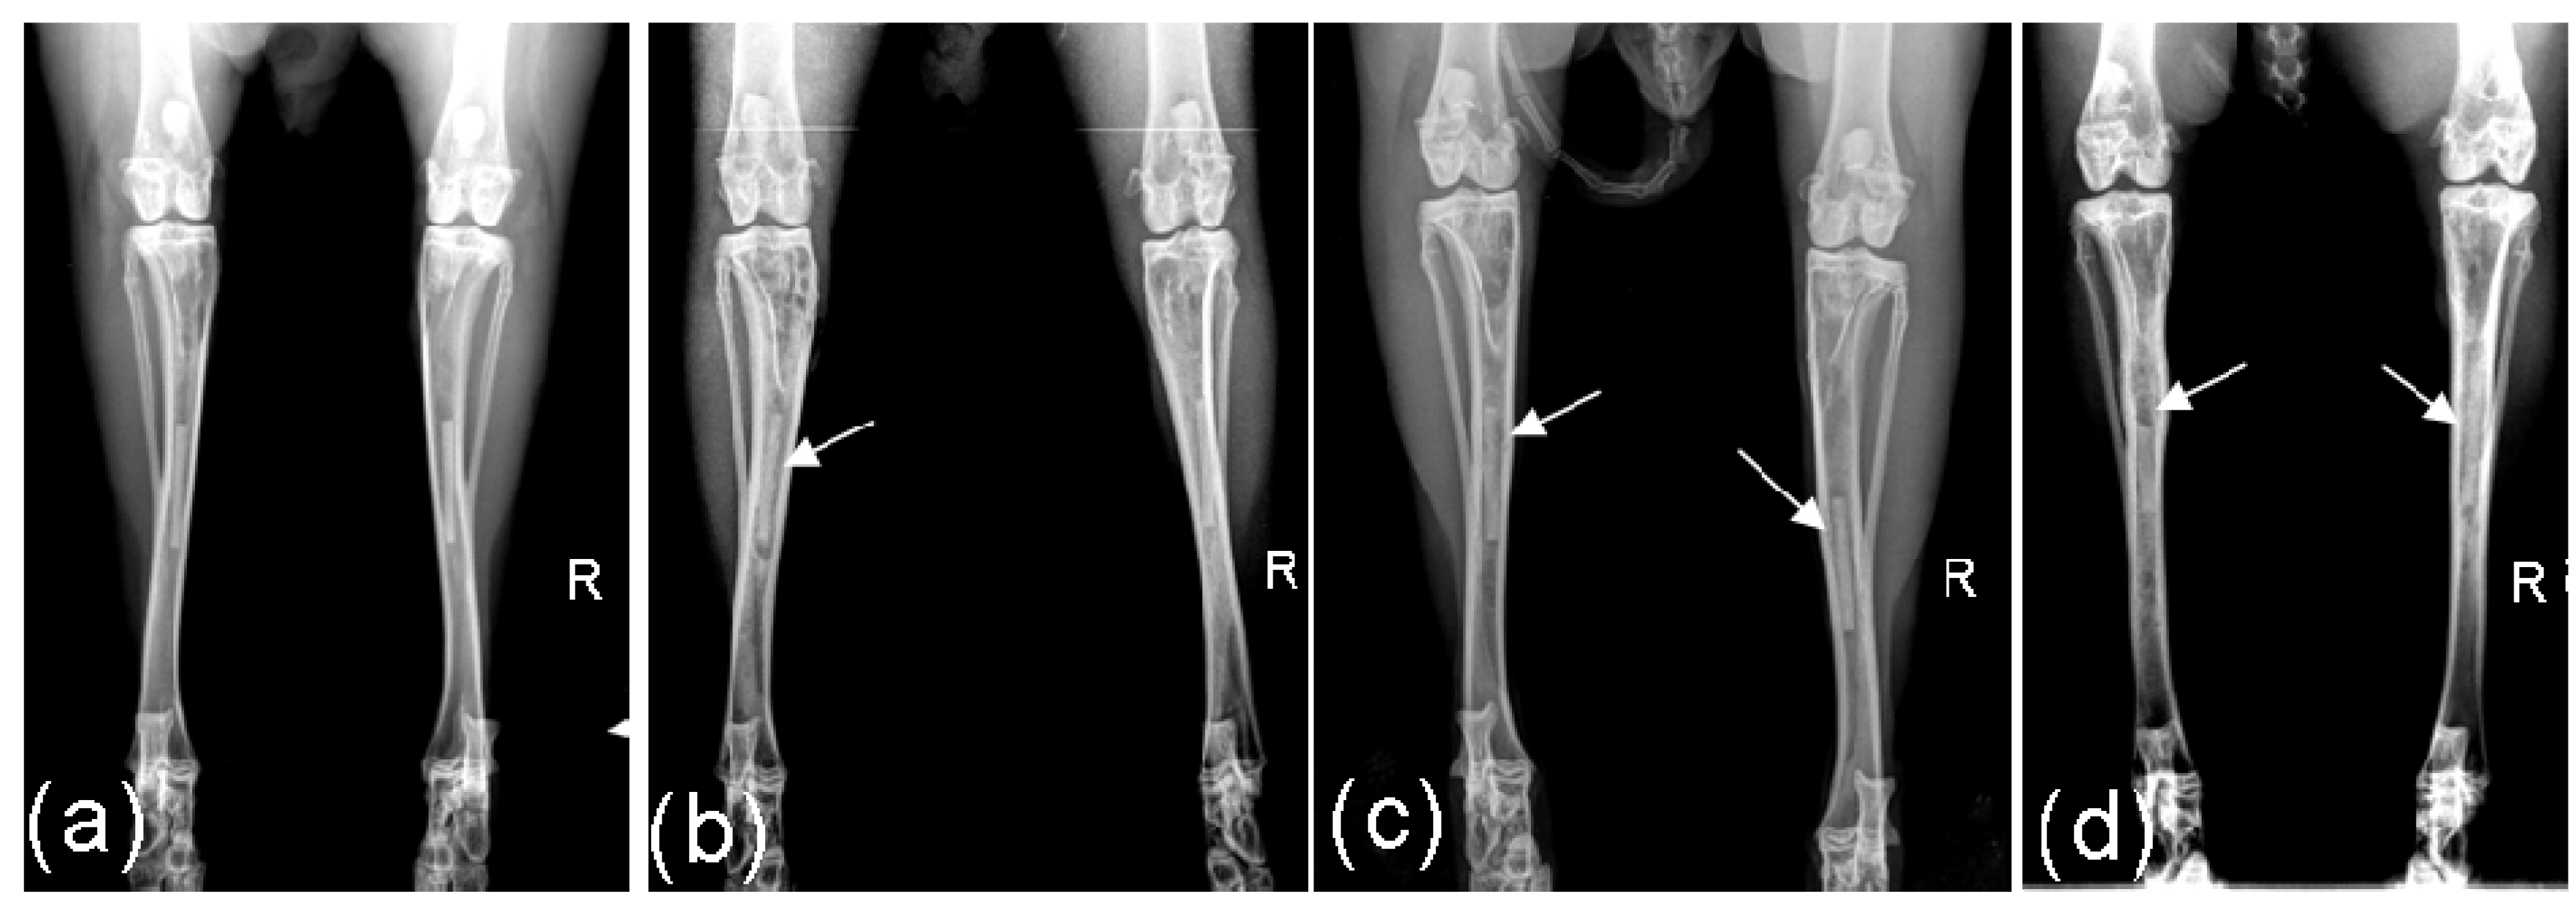

Figure 1.

Radiological images of implants: (a) after 4 weeks implantation period: Score left 0, right 0; (b) after 8 weeks implantation period: Score left 1, right 0; (c) after 13 weeks implantation period: Score left 1, right 1; (d) after 26 weeks: Score 3 and low level of gas formation left, score 2 right.

In the 4 weeks groups no implants demonstrated radiological changes. In the other three groups, three of the 26 implants were assessed with a score of 1 after 8 weeks. After 13 weeks, 8 of the remaining 16 implants obtained the score 1 and one implant the score 2. Following 26 weeks implantation, five of the remaining ten implants were assessed with the score 1, two with score 2 and two with the score 3 (Figure 1). During the entire 26 weeks monitoring time, only one implant remained radiologically unchanged.

In only two implants during the 8th and the 26th week, respectively, a low level of gas development could be detected.

The computed median was 0 over the entire time duration for the 4 and 8 weeks groups. The median attained a value of 1 in the 12th and 13th week for the 13 weeks groups. In the 26 weeks groups, the median value remained 1 from the 14th week to the end of the observation period.